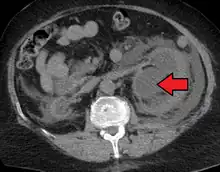

Renal ultrasonography of hydronephrosis caused by a left ureteral stone.

Imaging studies, such as an intravenous urogram (IVU), renal ultrasonography, CT, or MRI, are also important investigations in determining the presence and/ or cause of hydronephrosis. Whilst ultrasound allows for visualisation of the ureters and kidneys (and determine the presence of hydronephrosis and / or hydroureter), an IVU is useful for assessing the anatomical location of the obstruction. Antegrade or retrograde pyelography will show similar findings to an IVU but offer a therapeutic option as well. Real-time ultrasounds and Doppler ultrasound tests in association with vascular resistance testing helps determine how a given obstruction is effecting urinary functionality in hydronephrotic patients.[10]